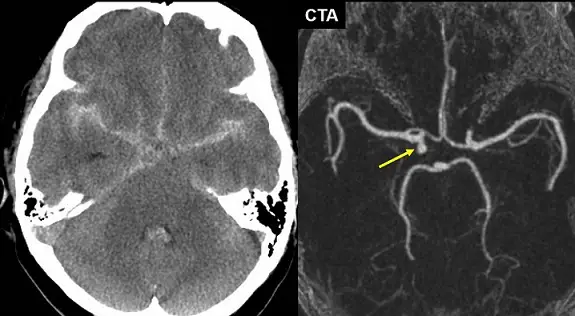

60歲女性因頭痛到急診就醫,根據所附頭部電腦斷層( CT )與電腦斷層血管造影( CTA )影像判斷,下列敘述何者正確?

從未增強頭部CT可見:

- 高密度出血聚積於基底顱窩區域,包括環繞中腦的環腦槽及眶下池,並向側裂及第三、四腦室輕度延伸

- 血液非限於腦 convexity,屬於suprasellar cistern with diffuse peripheral extension型態,此型態最常見於動脈瘤破裂所致SAH (recapem.com)

CTA三維重建可見: - 在前交通動脈複合體略偏右側處,有一顆錐狀或囊狀的動脈突出(箭頭所指),符合saccular aneurysm的經典影像表現

- 周邊血管經走形清晰,未見典型動脈壁內血腫或雙腔跡象,不支持動脈剝離